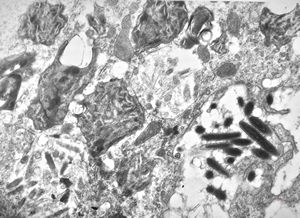

M,54y. | Whipple disease - duodenum